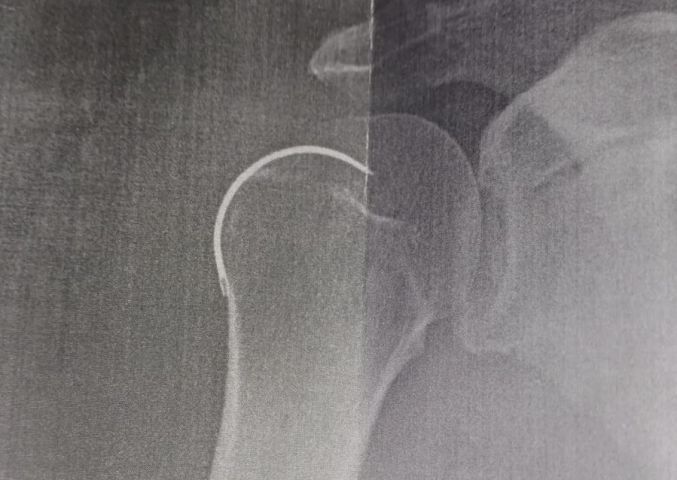

Josoel Geraldo Serafim, de 62 anos, é morador de Capivari de Baixo e passou por uma cirurgia no ombro direito no dia 6 de outubro de 2024, no Hospital Santo Antônio, em Armazém. No entanto, o procedimento teve uma grave falha: o médico esqueceu uma agulha de sutura dentro do ombro do paciente.

Por cinco meses, Josoel enfrentou dores constantes e procurou atendimento médico diversas vezes. Em todas as consultas, foi informado de que os sintomas eram normais no pós-operatório. Somente após um novo raio-X, os médicos descobriram a presença do objeto cirúrgico esquecido.